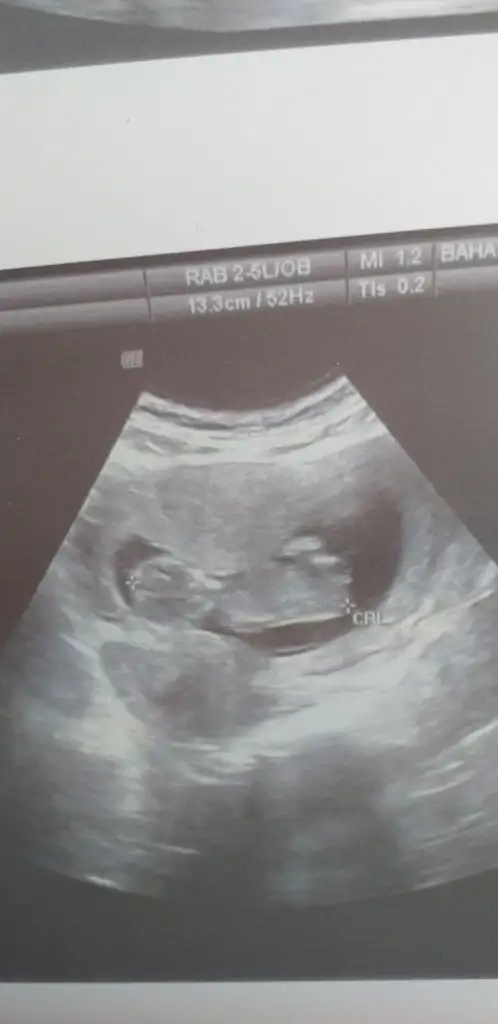

13 haftalik burada 16 da gelin dedi doktorum. bakalim tesekkur ederim cok cokKaç haftalık sanki kız gibi ama 11+ yada 12+ olmalı usg buyuk görünüyor gibi 13+ sonrası organ tamamlanmış oluyortam emin değilim tahminimden kız gibi gibi diyorum

İlk usgdeki nubu tam dik degil yakınlaştırınca bozuluyor foto digerleri net değil başka varsa tahmin ederim tam dik degil paralelde değil kafa yapısınıda ekledim kızda karar verdim aslında kızda olmayada bilir

Net degil 11 yada 12 hafta olmalı nub içinBunada bakabilirsiniz kizlar